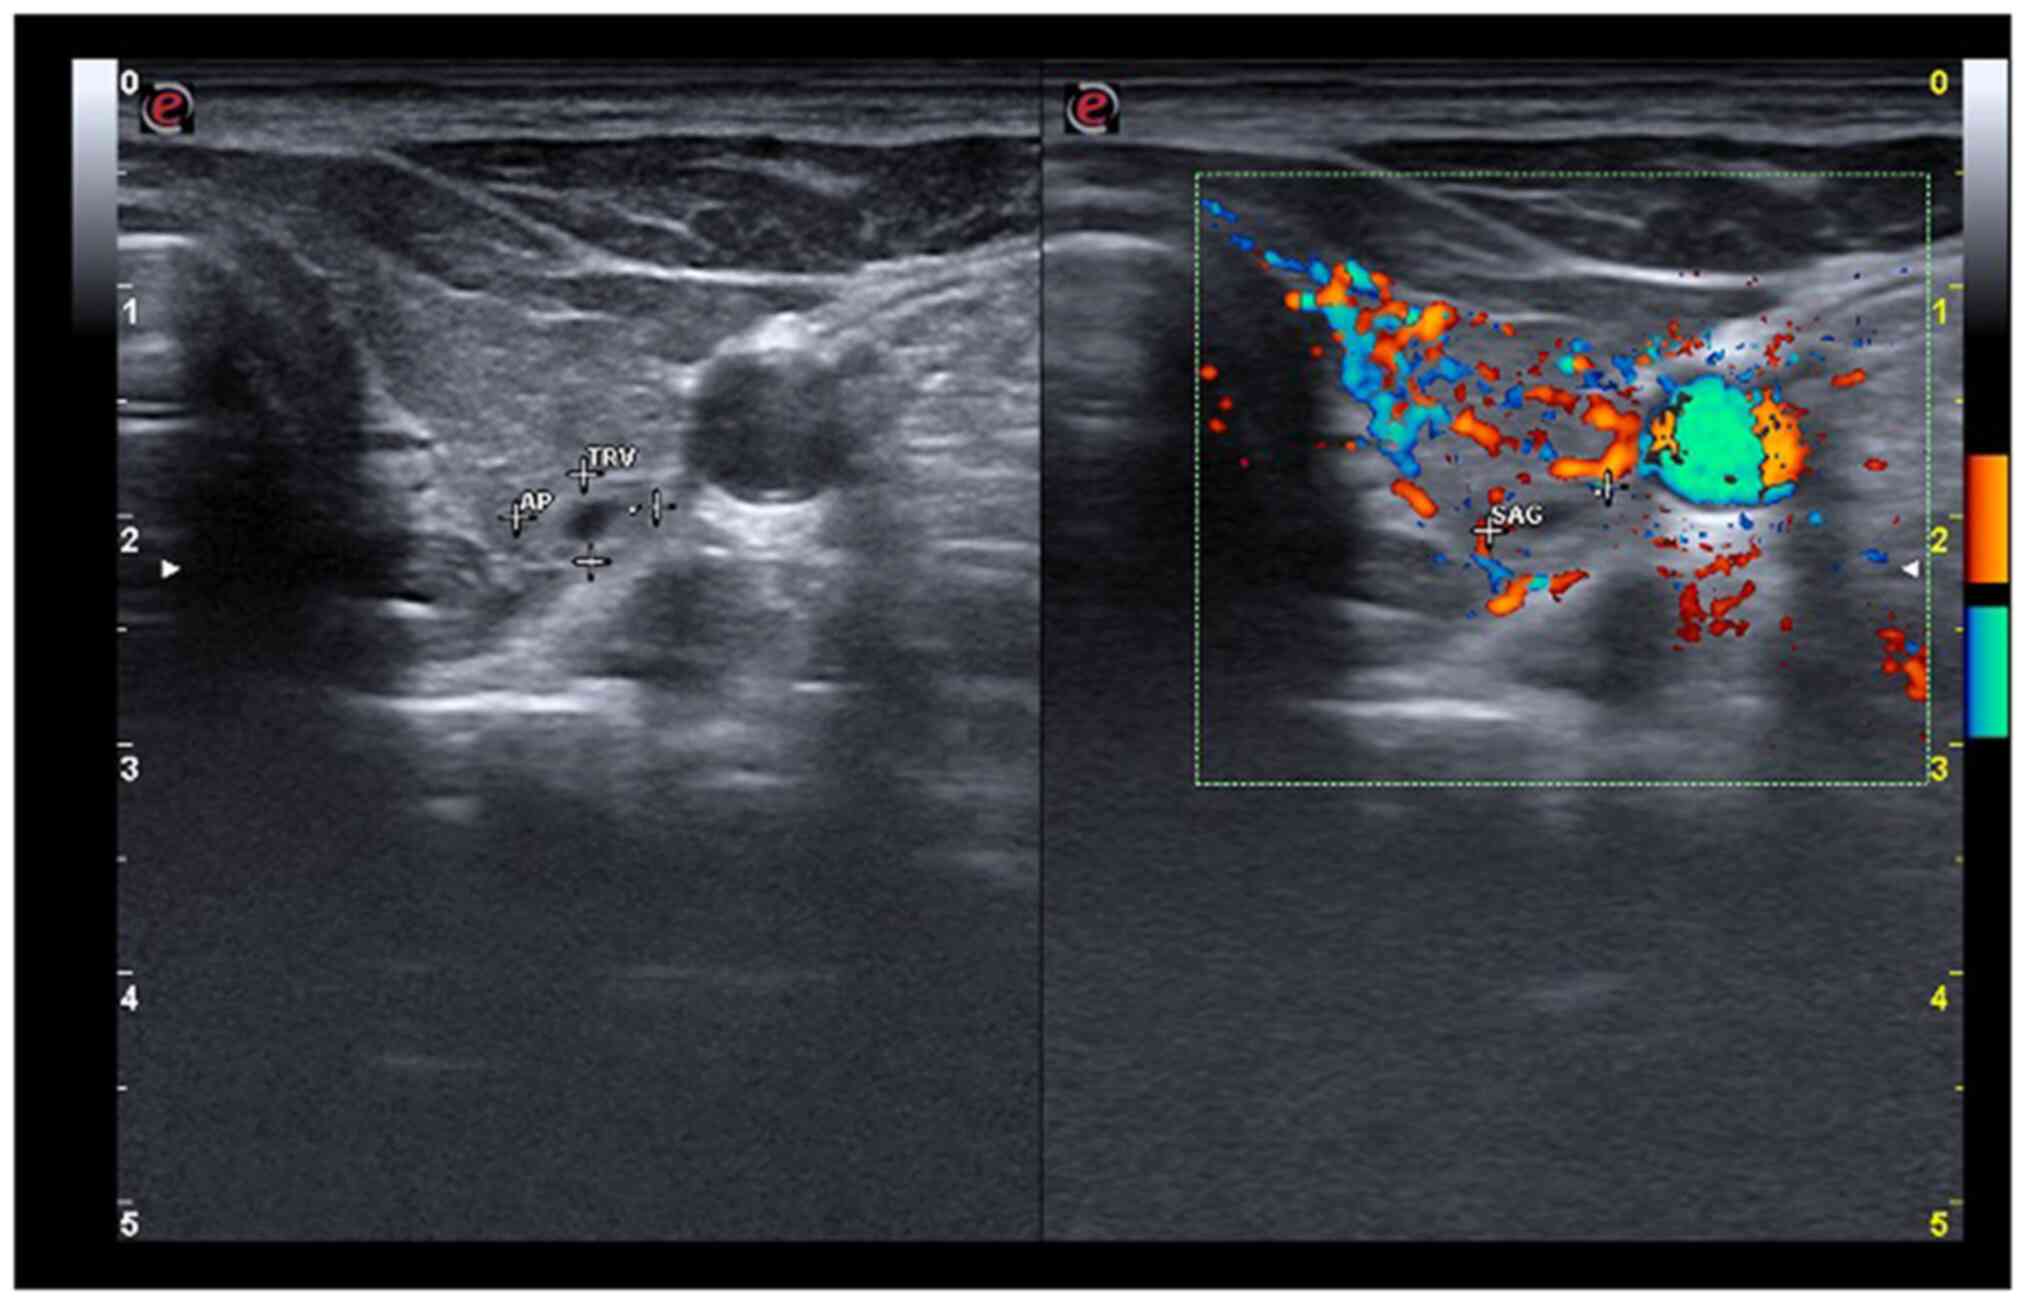

The neck ultrasound detected a hypoechoic thyroid parenchyma with an increased volume of the thyroid (26.8 ml, upper normal limit <16 ml). The right lobe was completely replaced by a spongiform nodule, with increased vascularity (Fig. 1), which was classified as benign by ACR-TIRADS (score 2) (15). The left lobe exhibited increased vascularity and, close to the posterior capsule, there was a partially cystic nodule of 6/5/7 mm (Fig. 2), also classified as benign by ACR-TIRADS (score 2).

Figure 1

Right thyroid lobe is replaced by a spongiform nodule (transverse plane).

Figure 2

Increased vascularity in the left thyroid lobe and a solid nodule near the posterior capsule (transverse plane).